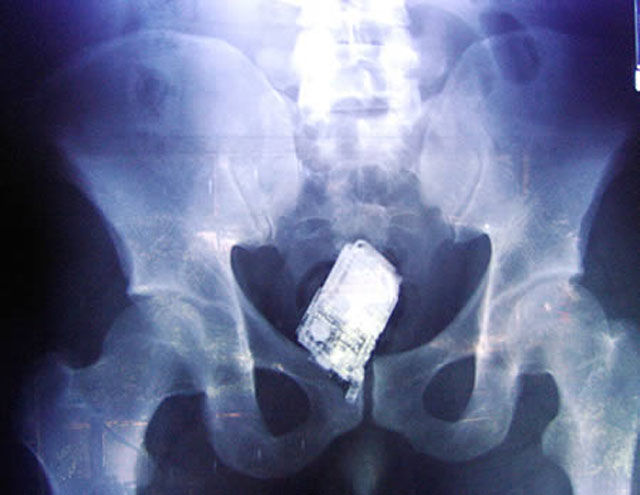

This X-ray reveals a cell phone lodged in a Salvadoran prisoner's lower intestine. The man is one of four prisoners who are members of the Mara Salvatrucha street gang. The men were caught with cell phones, spare chips and a charger that they had attempted to smuggle, according to authorities at San Salvador's Zacatecoluca prison.